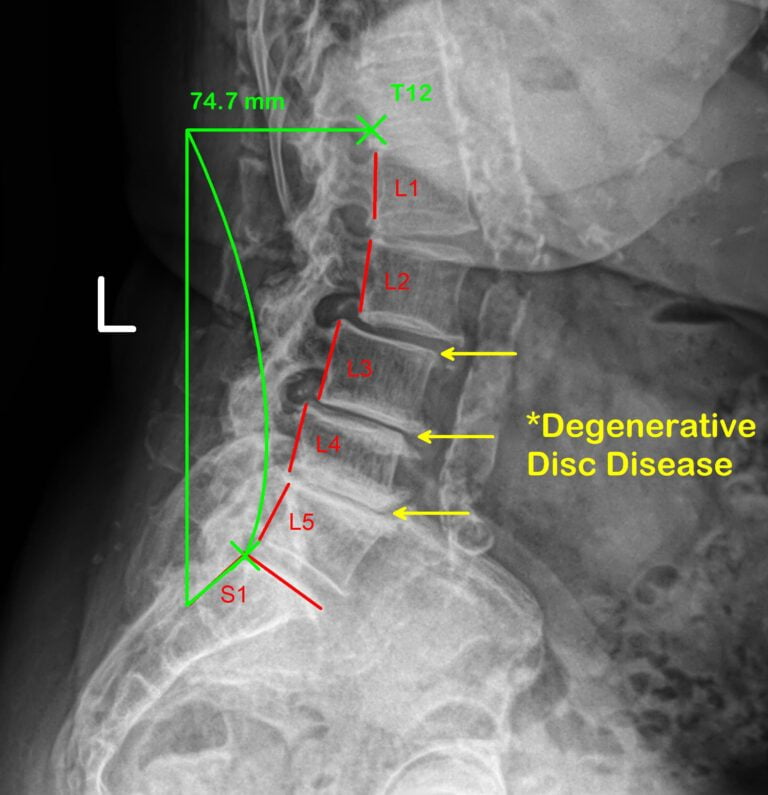

Treating Degenerative Disc Disease With Non Surgical Treatments

Degenerative disc disease impacts nearly 40% of people by age 40. Non-invasive approaches offer hope for maintaining function and quality of life, keeping surgery as a last resort.